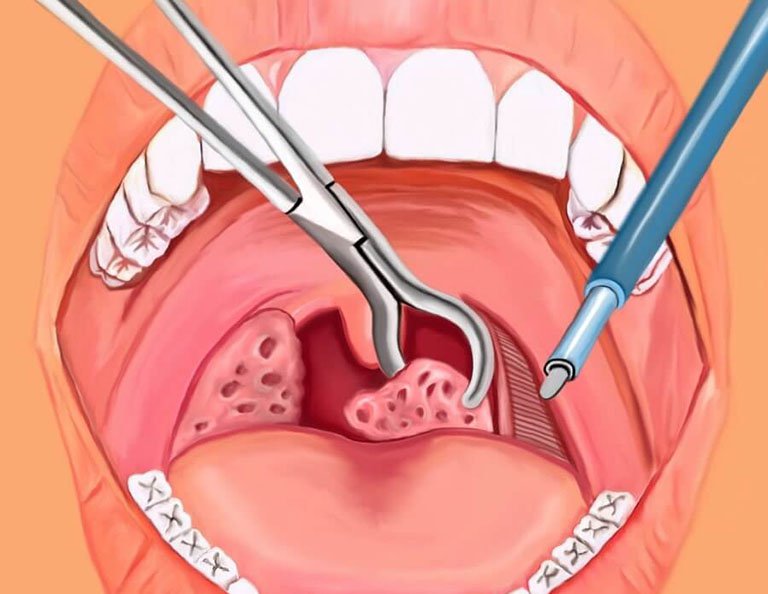

Ở trẻ em, khi viêm amidan bị tái đi tái lại nhiều lần, bố mẹ thường có xu hướng đưa trẻ đi cắt. Trên thực tế, cắt amidan hiện được đánh giá là biện pháp đem lại hiệu quả cao do loại bỏ tức thì vùng amidan bị viêm. Tuy nhiên, theo khuyến cáo của Tổ chức Y tế thế giới (WHO), amidan được chỉ định cắt trong những trường hợp:

- Viêm amidan gây biến chứng viêm xoang, viêm cầu thận, viêm khớp…

- Viêm amidan bị tái phát 5 – 6 lần/năm

- Viêm amidan gây hôi miệng nuốt vướng hoặc nghi ngờ ác tính

Buổi tư vấn truyền hình trực tuyến chủ đề “Giải pháp giúp thoát khỏi viêm họng, viêm amidan tái phát hiệu quả” vào 15h00, thứ Hai, ngày 9/10/2017, BSCKII Phạm Hưng Củng – Nguyên Vụ trưởng Vụ Y học cổ truyền, Bộ Y tế chia sẻ: “Nhiều bố mẹ cứ nghĩ cho trẻ cắt amidan là khỏi, nhưng amidan là tổ chức bảo vệ cơ thể chống lại các tác nhân gây bệnh từ bên ngoài.

Tuỳ tiện cắt bỏ amidan không những tốn kém chi phí, mất thời gian chăm sóc sau phẫu thuật mà còn để lại hậu quả làm mất đi hệ thống miễn dịch, sức đề kháng của cơ thể, có thể dẫn tới tử vong do chảy máu trong và sau cắt amidan. Thậm chí, nhiều trẻ tuy đã hết viêm amidan nhưng lại bị viêm họng mạn tính, viêm thanh quản sau cũng gây mệt mỏi, nguy hiểm không kém”.